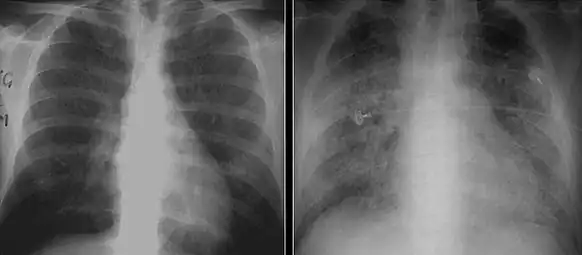

These chest radiographs are of two patients. Both show ground glass opacities. The left X-ray shows a much more subtle ground-glass appearance while the right X-ray shows a much more gross ground-glass appearance mimicking pulmonary edema.[6]